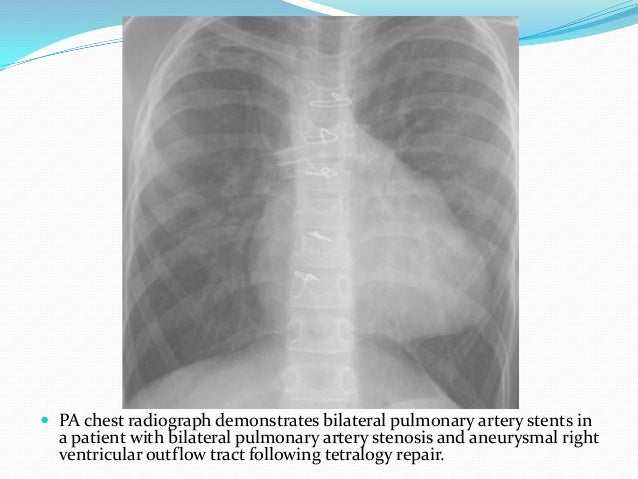

radiopaedia.org

Medical Devices On The Chest X Ray

www.slideshare.net